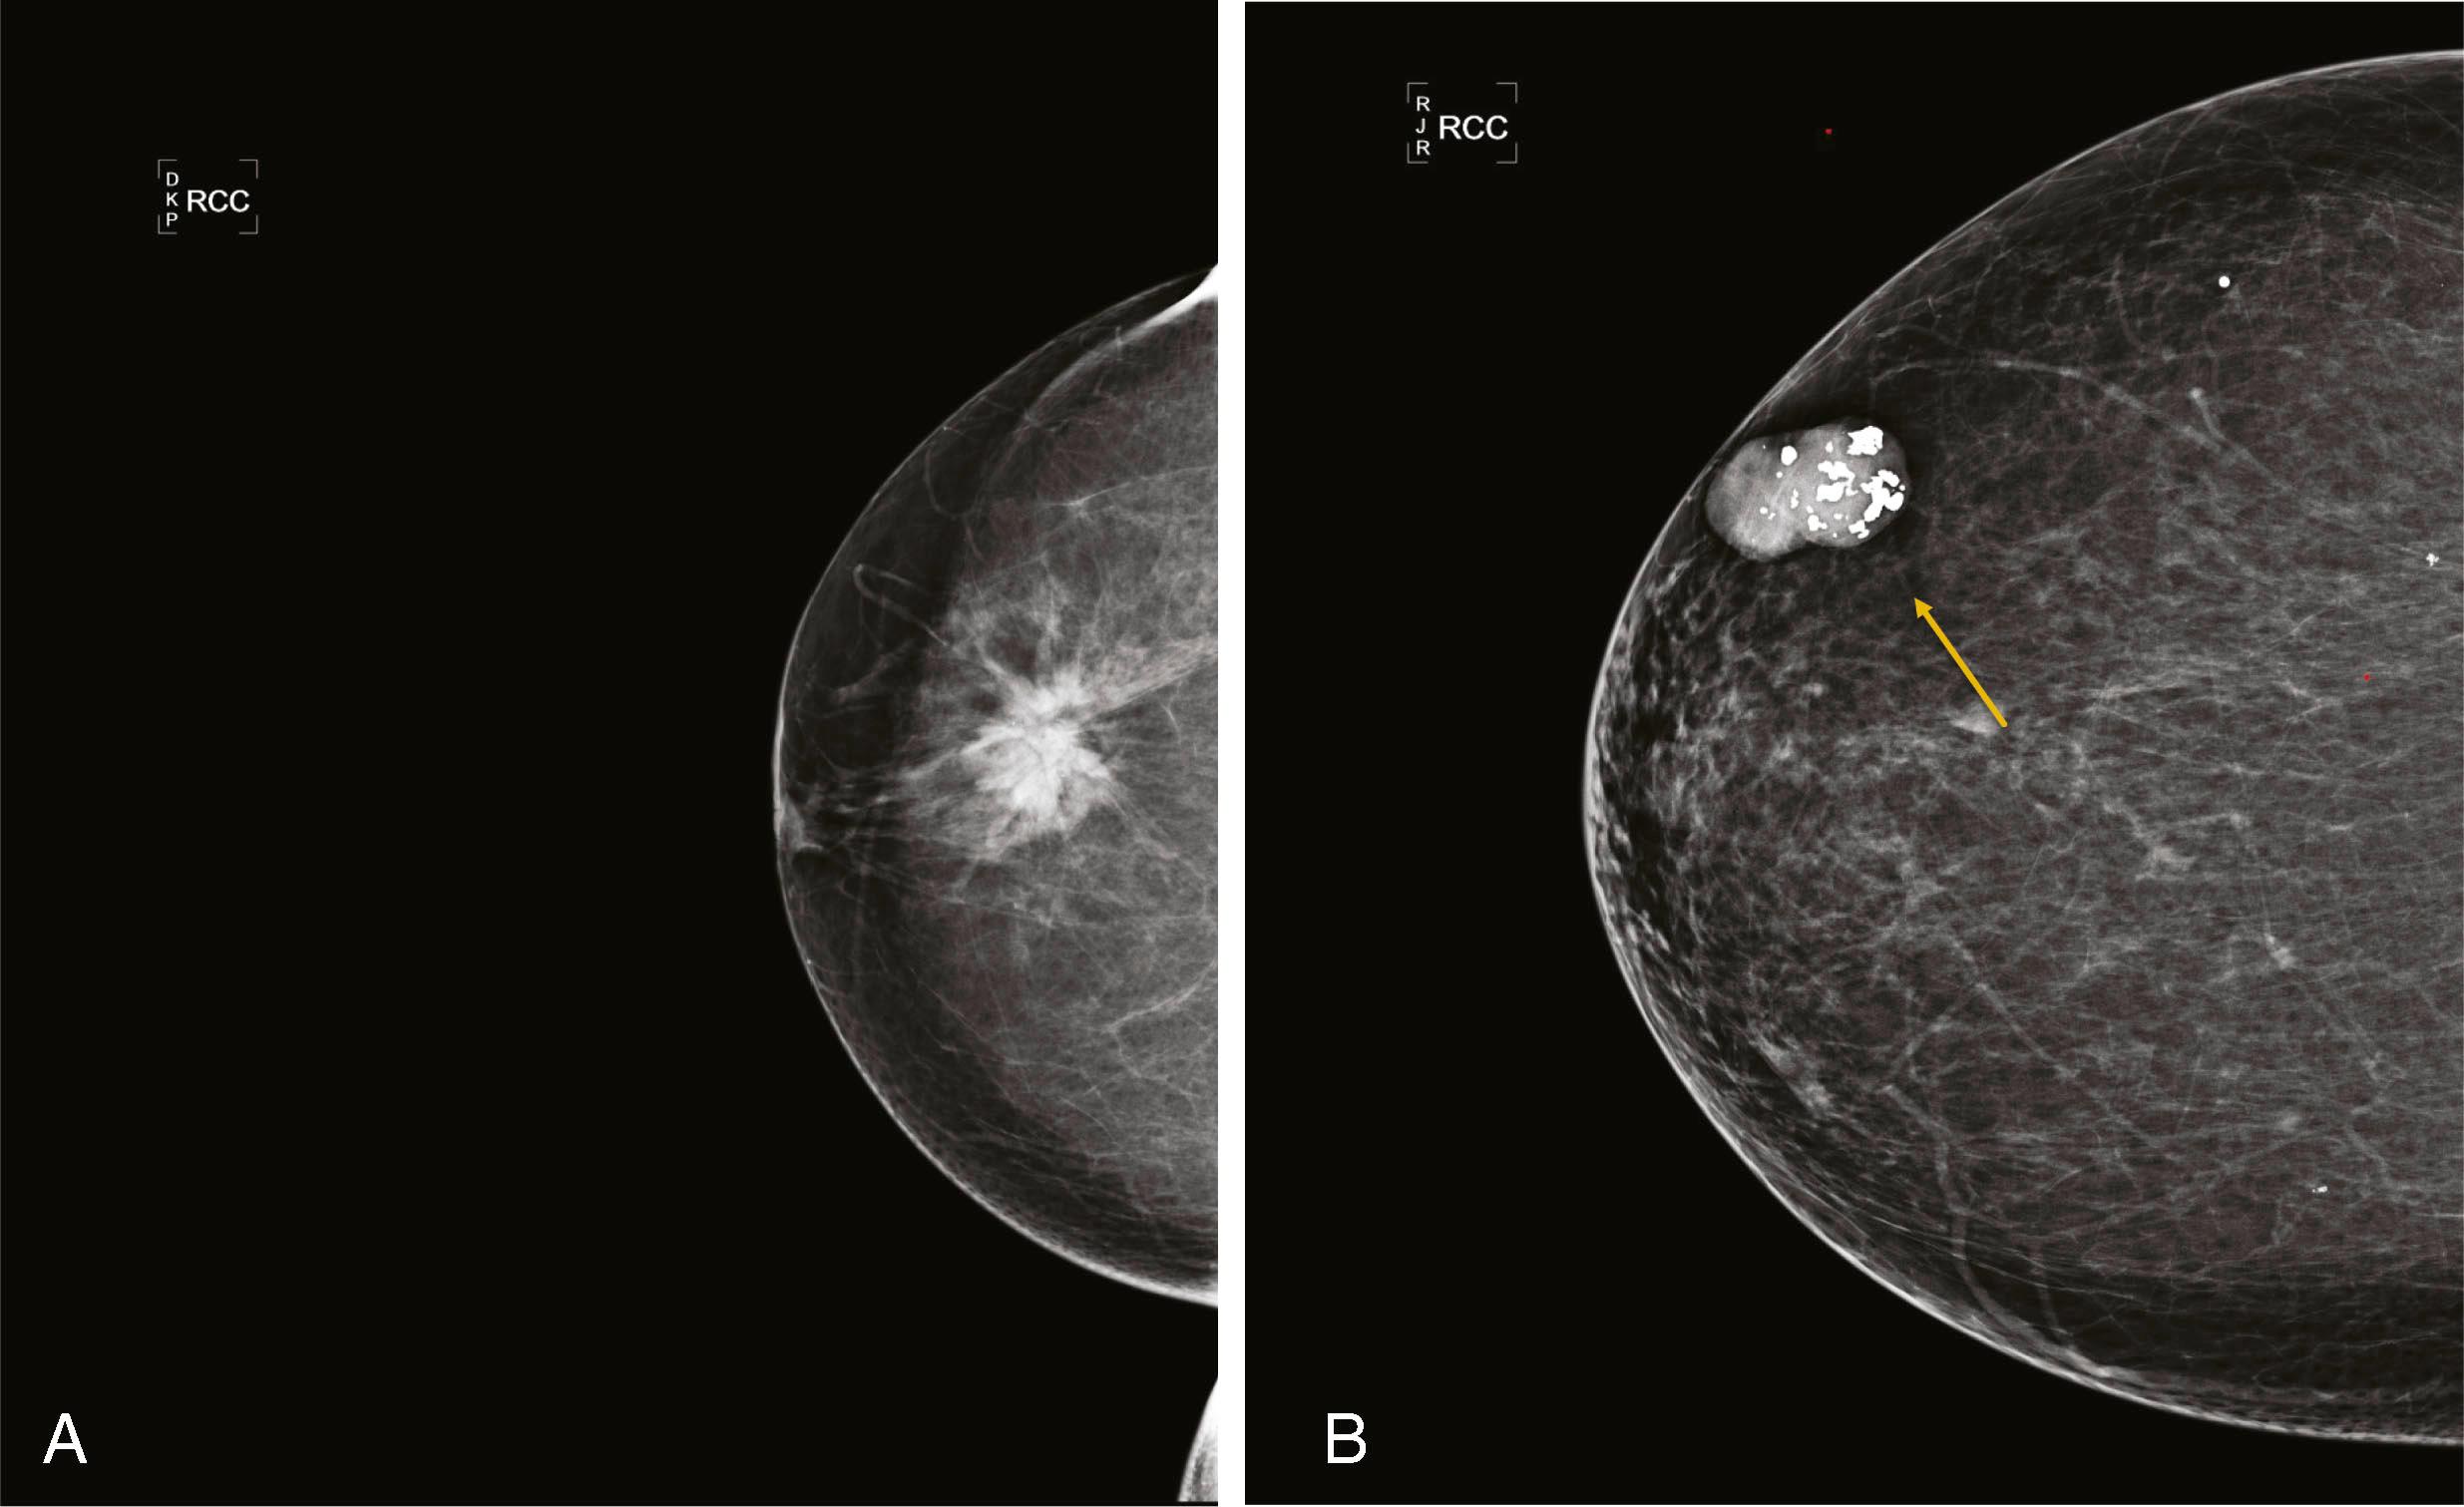

Microcalcifications can be associated with benign and malignant processes. Pleomorphism, linear shape and orientation, and clustered or segmental distribution of calcifications suggest malignancy, whereas a more diffuse distribution and rounded shape favor a benign etiology. Magnified views in the CC and ML (true lateral) projection are performed to more accurately assess their morphology. Certain features of calcifications such as central lucency or meniscal layering are classic for benign disease, but often the calcifications cannot be categorized as benign or malignant and are reported as “indeterminate.” Stereotactic biopsy is recommended for suspicious calcifications and usually for indeterminate calcifications, whereas 6-month follow-up mammography is advised for those thought to be probably benign ( Fig. 8.5 ).

Masses are evaluated mammographically with spot compression, spot-magnified views, or tomosynthesis to better visualize their margins. Smooth margins suggest a benign etiology, whereas irregular, microlobulated, ill-defined, or spiculated margins suggest malignancy. Large, coarse calcifications in a well-defined mass are typical features of a fibroadenoma ( Fig. 8.6 ).

Fig. 8.6, ( A ) Craniocaudal (CC) view of a spiculated mass. Core biopsy revealed invasive duct carcinoma and ductal carcinoma in situ, nuclear grade 2. ( B ) CC view of a typical calcifying fibroadenoma (arrow) .